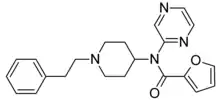

Anilidopiperidines